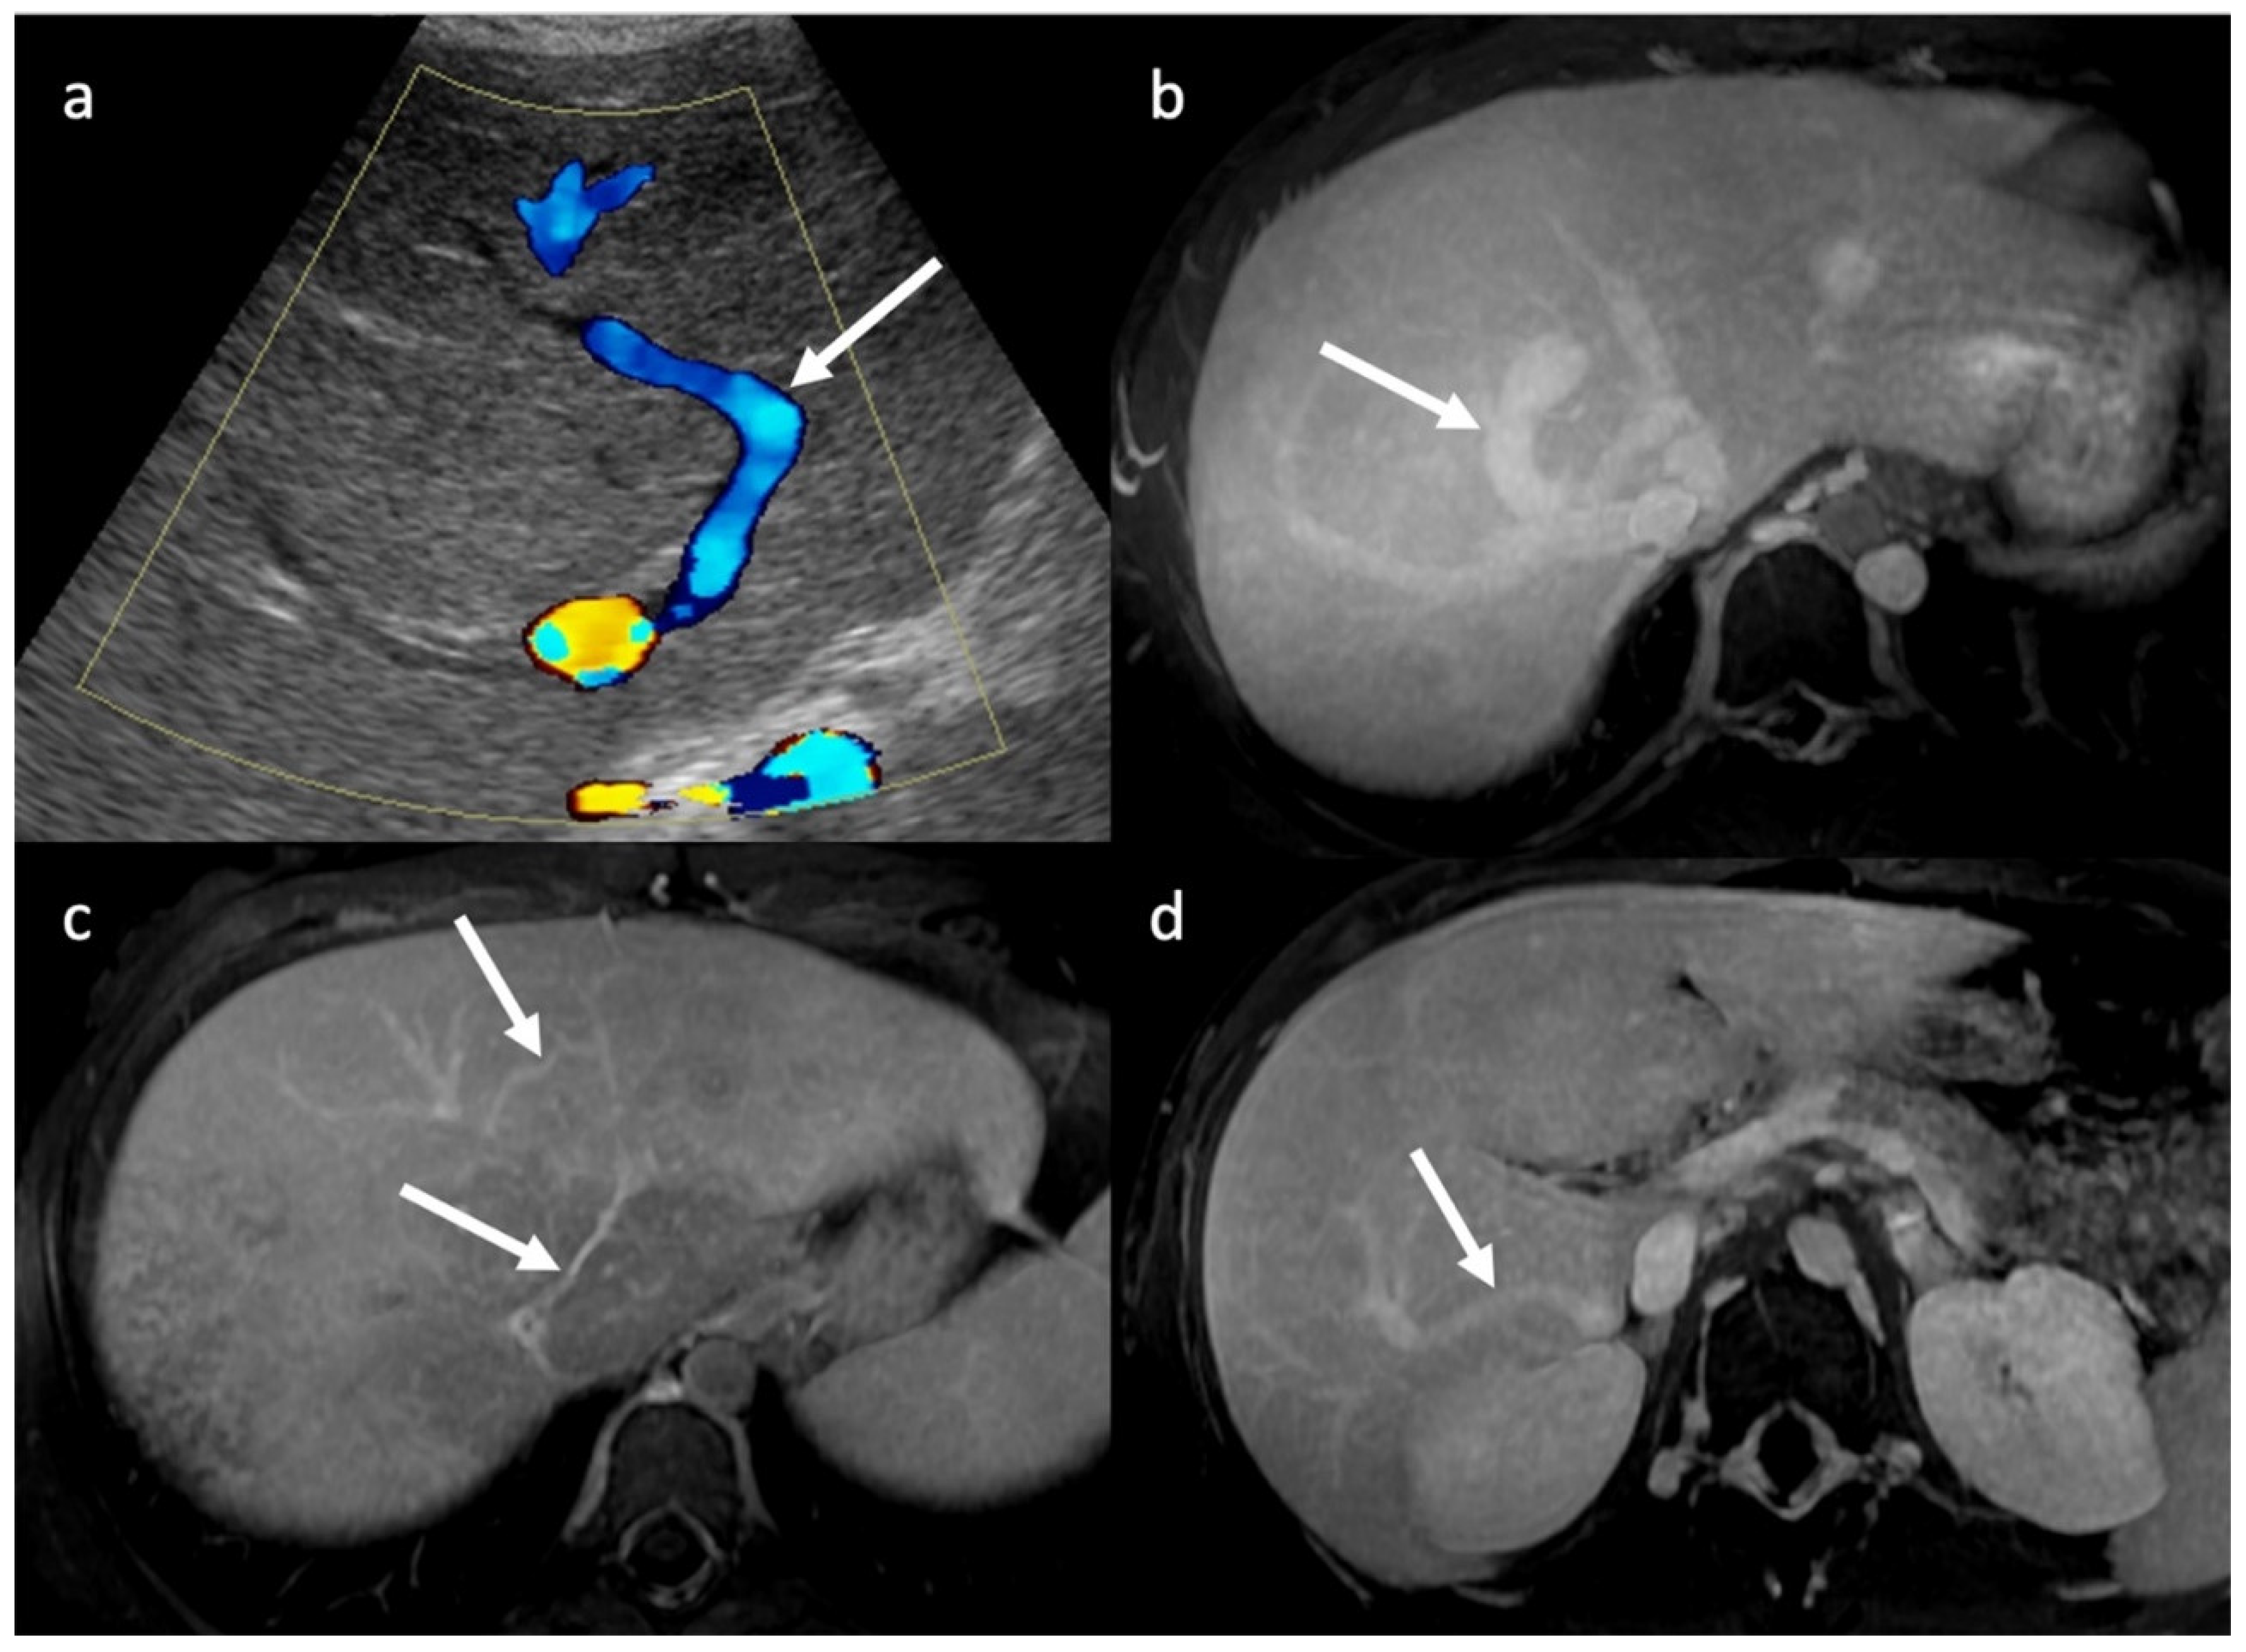

3.1. Ultrasounds: What to Look For

3.2. Computed Tomography and Magnetic Resonance: What to Look For

| CDUS | HV thrombosis ICV thrombosis and compression (better studied on CT/MRI) PV thrombosis HV demodulation Intra-hepatic collateral vessels Stagnant, reduced and/or hepatofugal PV flow Focal acceleration of velocity corresponding to stenosis Ascites Caudal lobe enlargement |

| CT | Liver morphology alteration Acute phase: “zonal” or “flip-flop” perfusion Chronic phase: “mosaic” perfusion Extra- and intra-hepatic collaterals Site and extension of thrombosis Pre-endovascular treatment assessment Hepatic artery and caudate vein enlargement Hepatic Nodules Ascites and caudal lobe enlargement |

| MRI | Characterization of nodules (FNH-like nodules vs. HCC) T1-w decreased signal in hypoperfused regions, corresponding to high T2-w SI T2*-w flow void corresponding to thrombus. Hypointensity along the occluded vessels |